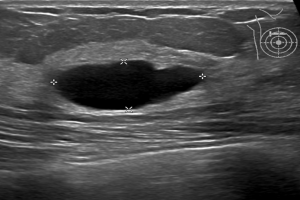

La ecografía mamaria es el método de imagen más utilizado después de la mamografía. Es ampliamente aceptado como un estudio de forma aislada o como complemento de ésta. Permite obtener imágenes de gran calidad para detectar lesiones muy pequeñas como microcalcificaciones. También es capaz de caracterizar nódulos mamarios, ayudando a diferenciar lesiones benignas de lesiones malignas.